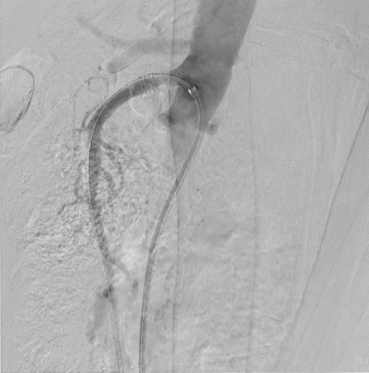

患者取仰卧位,常规消毒铺巾,1%利多卡因局麻后,逆行穿刺右侧股动脉,置入6F血管鞘,泥鳅导丝配合猪尾导管送至胸12水平,正位及侧位造影见肠系膜上动脉起始部钙化严重,可见支架影,支架内重度狭窄,肠系膜上动脉中远段延迟显影。经右股动脉入路更换7F 55cm RDC长鞘,导丝、导管配合选入肠系膜上动脉并通过病变段,建立轨道。沿导丝送入4mm球囊扩张病变段,扩张后造影见肠系膜上动脉支架内狭窄较前有所改善。再沿导丝送入7mm✖60mm震波球囊,扩张后再次造影示:肠系膜上动脉显影较前明显改善,支架内造影剂通过顺利,未见明显残余狭窄,无造影剂外溢,遂决定结束手术,缝合器缝合穿刺点,无菌敷料加压包扎,手术过程顺利,术后患者安返病房。

术后造影

术后 造影侧位

术后 造影正位

该病例的临床难点在于患者高龄,肠系膜上动脉支架植入术后,支架内反复再出现狭窄,且患者出现腹痛症状;考虑支架内斑块形成,内膜增生,传统球囊单纯扩张难以达到治疗效果;采用Shockwave IVL冲击波导管技术,通过低压冲击波能量可以有效将钙化斑块裂解,使血管在低压状态下安全扩张,避免了传统方法的高风险。术后造影显示血流通畅,无远端血管栓塞,无造影剂外溢,显著改善了血流,患者术后恢复良好,腹痛症状消失。相信,Shockwave IVL技术将在更广泛的钙化病例中得到应用,提高钙化病变的远期通畅率及患者预后。